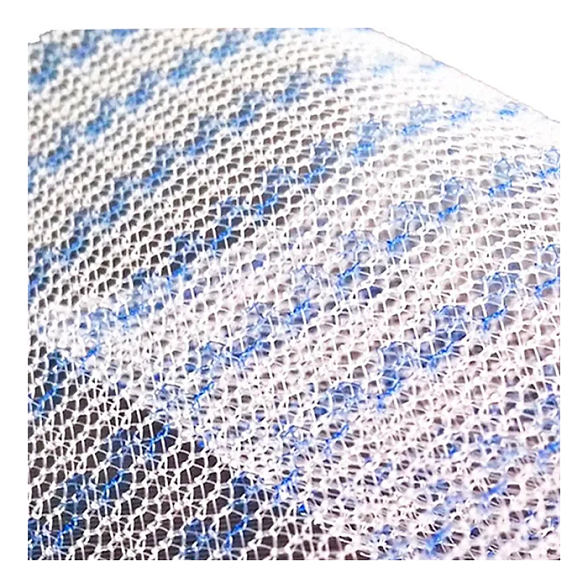

Эндопротез-сетка ЭСФИЛ — это современный, высококачественный хирургический имплантат, предназначенный для восстановительной и пластической хирургии. Изделие производится из инертного медицинского полипропилена, что обеспечивает его биосовместимость и надежную интеграцию в ткани организма. Сетка стандартного размера 30х30 см является универсальным решением для широкого спектра оперативных вмешательств, где требуется укрепление или замещение мягких тканей.

Ключевым преимуществом сетки ЭСФИЛ от «Линтекс» является ее макропористая структура. Это позволяет тканям пациента свободно прорастать через ячейки имплантата, формируя прочный соединительнотканный каркас и минимизируя риск осложнений, таких как отторжение или хроническая боль.

- Отличная интеграция: Макропористая структура способствует быстрому и полноценному прорастанию соединительной ткани, надежно фиксируя имплантат.

| Структура | Макропористая, монофиламентная или мультифиламентная (уточняется у производителя для конкретной модификации) |